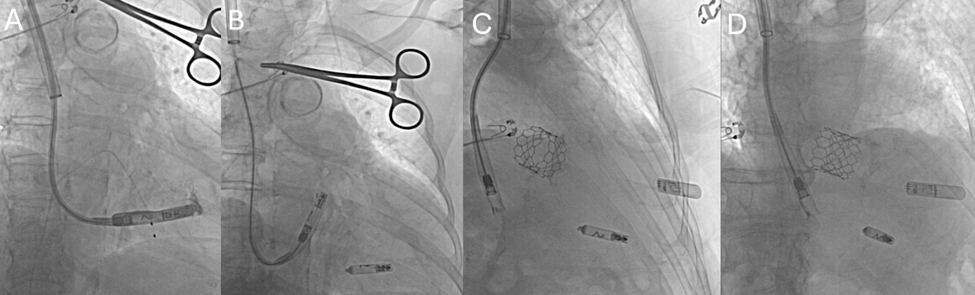

All procedures were performed under fluoroscopic guidance. Venous access was obtained in the RIJ vein under ultrasound guidance. A single Perclose ProGlide suture (Abbott) was deployed and secured with hemostats using the preclose technique. Serial dilatation allowed placement of the AVEIR delivery sheath. In cases of AVEIR VR, the sheath was advanced into the right atrium and carefully manipulated across the tricuspid valve into the right ventricle. Device deployment was performed at the right ventricular septum, and stability was confirmed with the standard tug test. Electrical performance was assessed by measuring sensing and capture thresholds, and final device release occurred only after implant criteria were satisfied (Figure 2). The delivery sheath was subsequently removed, and hemostasis was achieved with ProGlide closure in all patients.